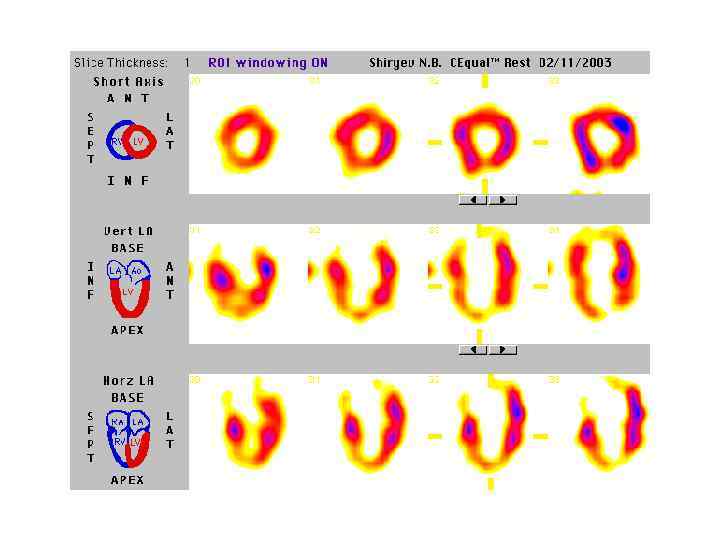

Систола Больной 58 лет. Жалобы: ангинозные боли, перенес задний ИМ. ВЭМ: 75 Вт, на пике нагрузки АД – 180/100 ЧСС 1200 уд/мин. Критерии прекращения пробы: ангинозные боли Диастола ЭКГ-синхронизированная ОФЭКТ миокарда Ангиография: Окклюзия ветви ПКА. Заключение: Гипоперфузия задней стенки ЛЖ в диастоле и систоле (рубец). Диастолическая гипоперфузия верхушки с улучшением накопления РФП в систоле свидетельствует о сохранении сократительной способности в этой области. 51 ЛКА ПНА ДВ ОА

Систола Больной 58 лет. Жалобы: ангинозные боли, перенес задний ИМ. ВЭМ: 75 Вт, на пике нагрузки АД – 180/100 ЧСС 1200 уд/мин. Критерии прекращения пробы: ангинозные боли Диастола ЭКГ-синхронизированная ОФЭКТ миокарда Ангиография: Окклюзия ветви ПКА. Заключение: Гипоперфузия задней стенки ЛЖ в диастоле и систоле (рубец). Диастолическая гипоперфузия верхушки с улучшением накопления РФП в систоле свидетельствует о сохранении сократительной способности в этой области. 51 ЛКА ПНА ДВ ОА